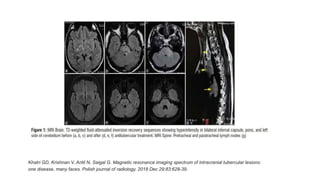

• Hyperintensity of internal capsule and diffuse hyperintensity in brain

stem and cerebellum without contrast enhancement

Khatri GD, Krishnan V, Antil N, Saigal G. Magnetic resonance imaging spectrum of intracranial tubercular lesions:

one disease, many faces. Polish journal of radiology. 2018 Dec 29;83:628-39.